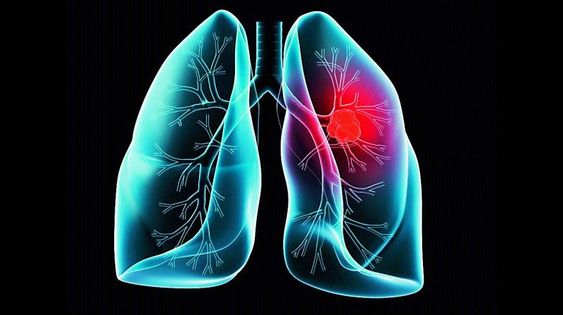

폐렴 증상 9. 입술이나 손끝이 푸르스름하게 변색 (청색증)

산소 포화도가 낮아지면서

입술, 손톱, 발끝이 보랏빛 또는 푸르스름하게 변하는 청색증이 생길 수 있습니다.

이는 폐렴이 상당히 진행된 상태일 수 있으므로 응급 상황입니다.10. 구토, 설사 등 소화기 증상